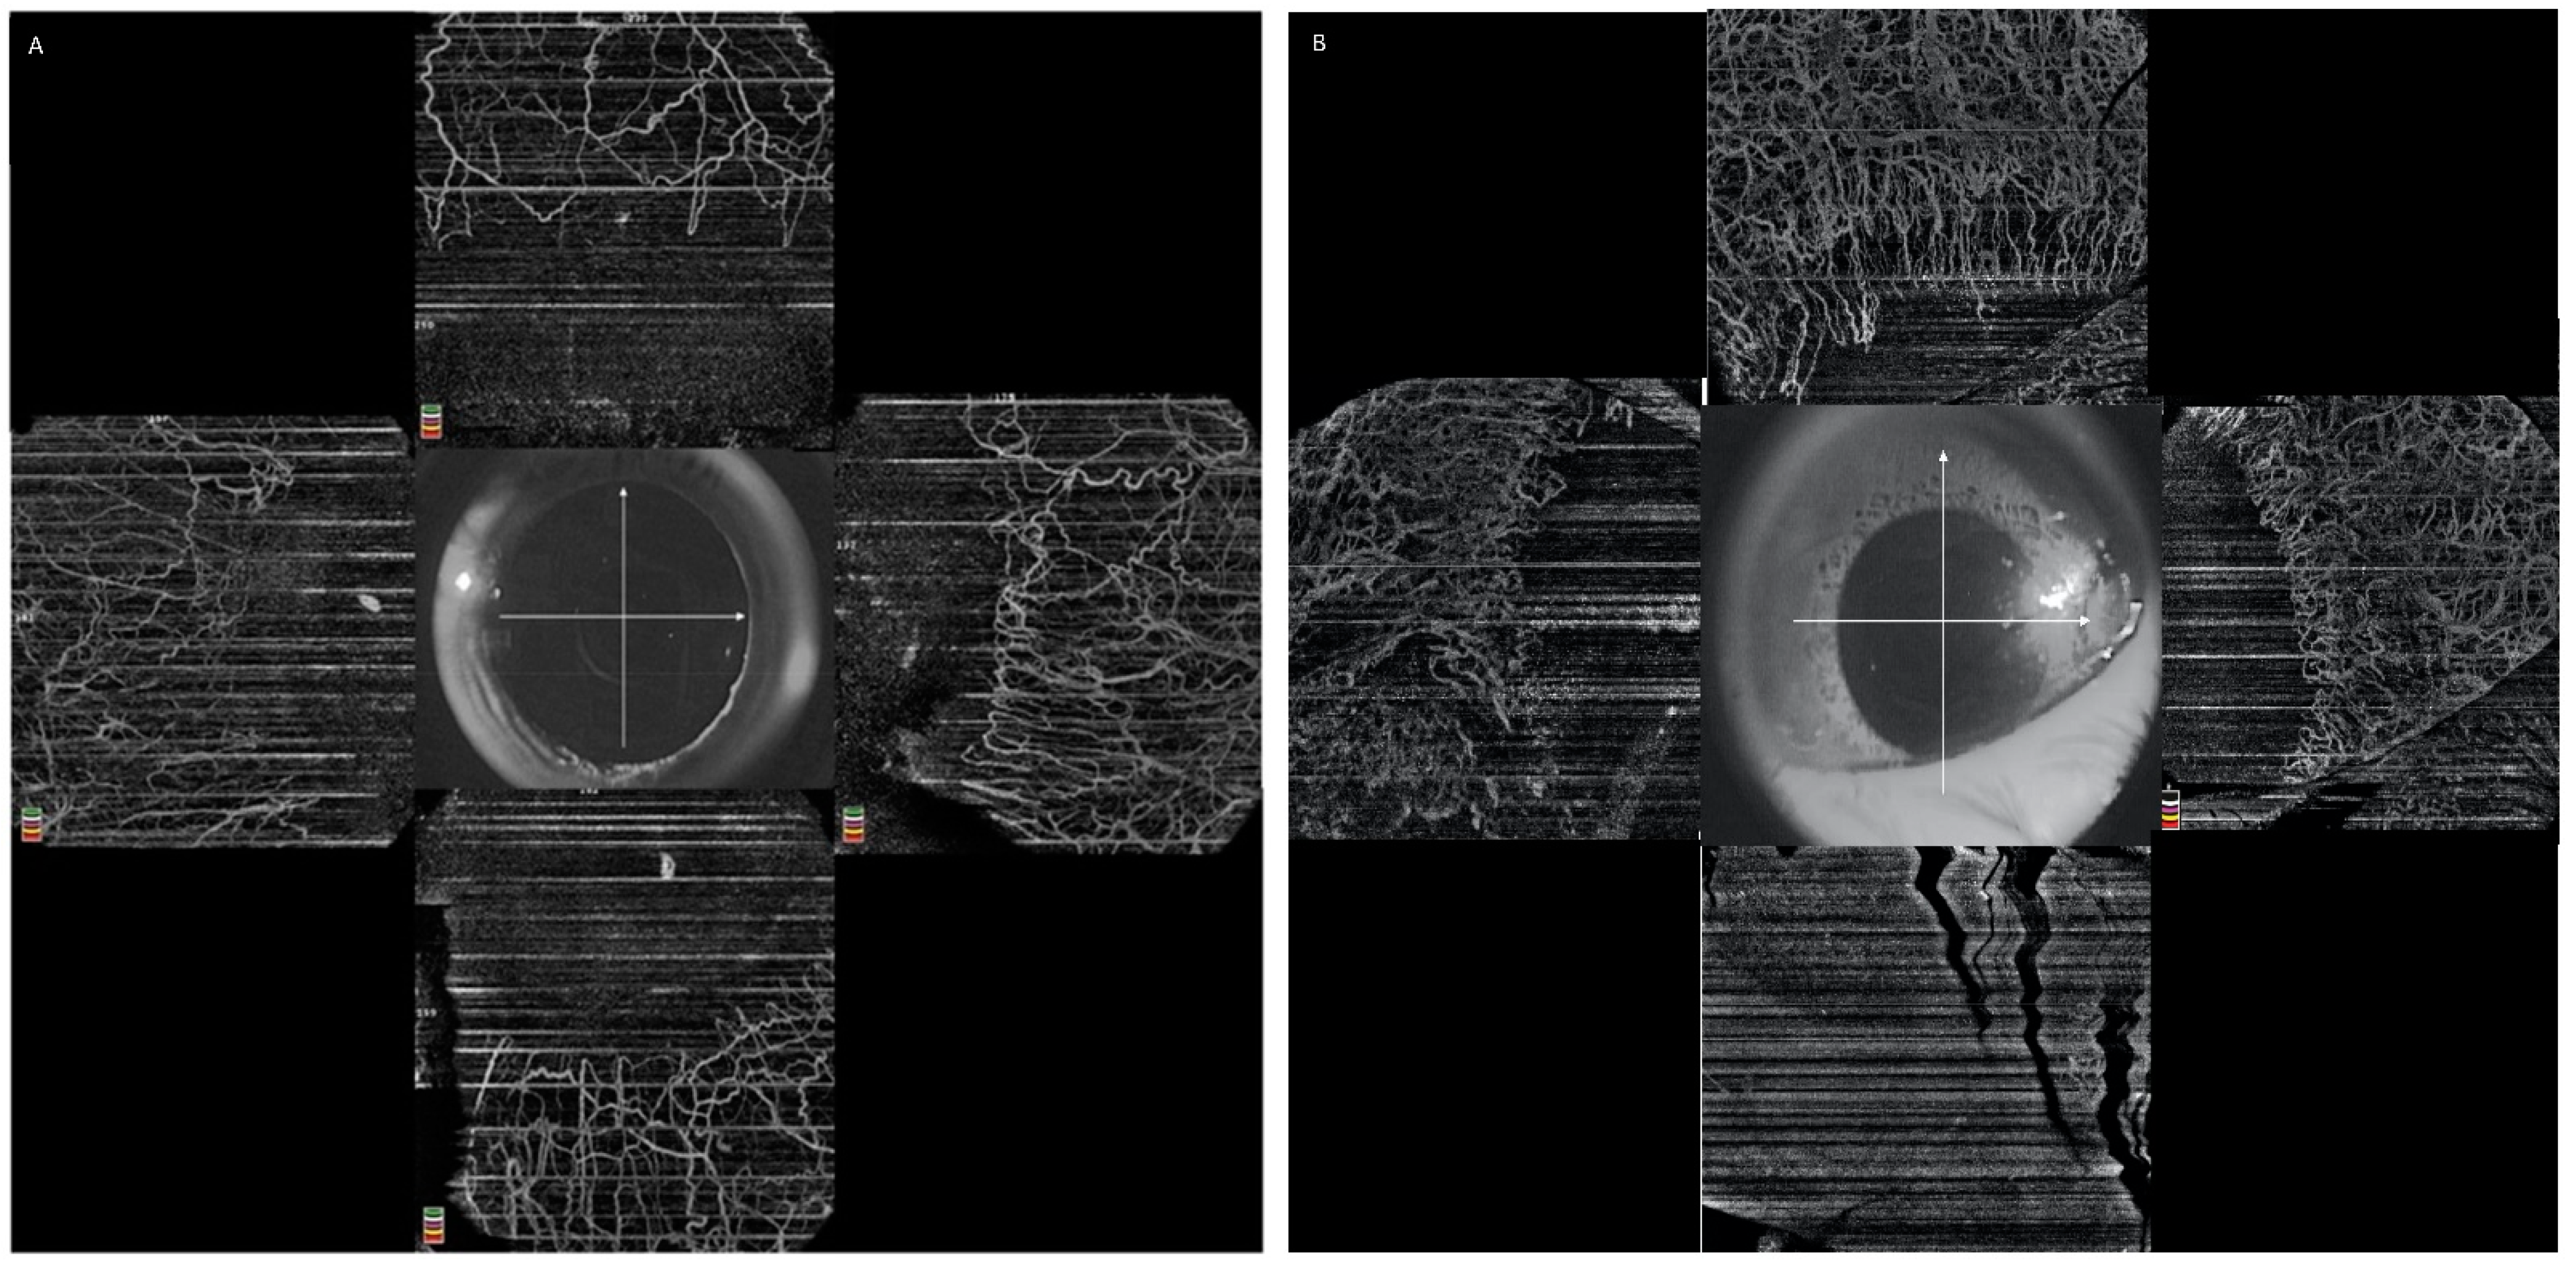

5.2.3. Qualitative Assessment of Limbal Vasculature

- Ang, M.; Foo, V.; Ke, M.; Tan, B.; Tong, L.; Schmetterer, L.; Mehta, J.S. Role of Anterior Segment Optical Coherence Tomography Angiography in Assessing Limbal Vasculature in Acute Chemical Injury of the Eye. Br. J. Ophthalmol. 2021. [Google Scholar] [CrossRef] [PubMed]